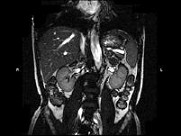

- 单项选择题男,52岁, 下肢无力伴多饮多尿2年余,实验室检查: 低血钾,血醛固酮水平及24h尿醛固酮定量超过正常值, MRI检查如图所示,应诊断为 ( )

A、左肾上腺囊肿

B、左肾上腺腺瘤

C、左肾上腺嗜铬细胞瘤

D、左肾上腺髓脂瘤

E、左肾上腺转移癌